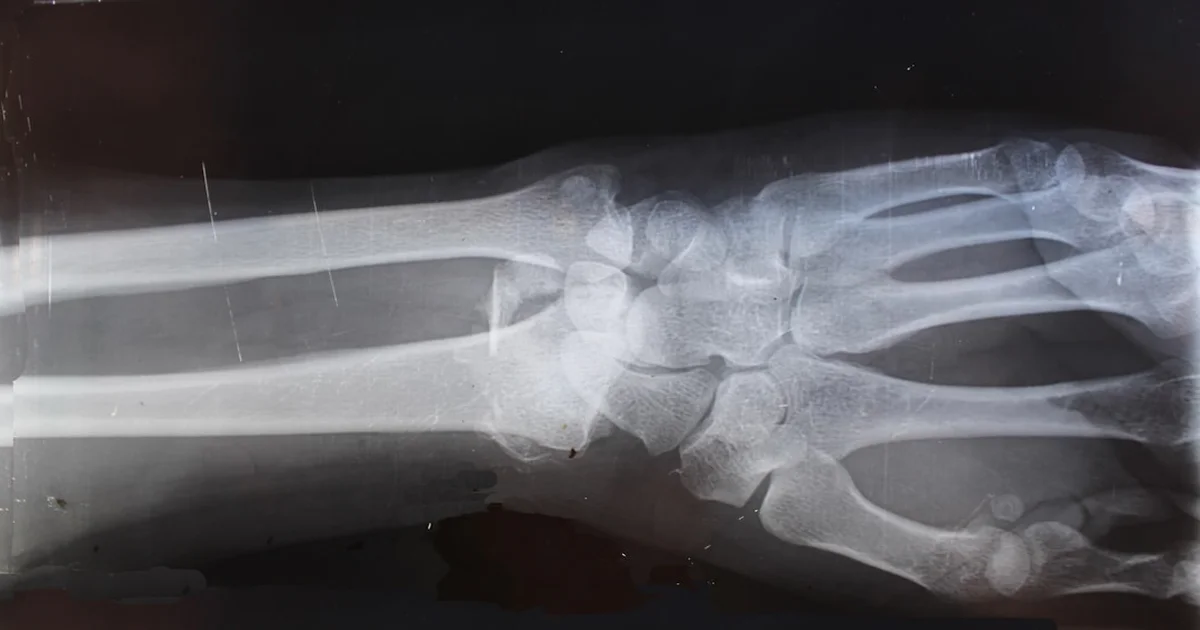

LONDON—The Sex Pistols tour reschedule has been announced. The legendary punk band will now hit the road in September. This follows a wrist injury to guitarist Steve Jones. Doctors cited extensive guitar-picking as the cause. Fans can now finally experience “Never Mind the Bollocks” live again. The original 2025 trek was postponed due to the ailment.

“Punk rock requires peak physical condition,” stated Dr. Agnes Plinkett, Chief Orthopedic Punkologist at St. Vibrator’s Hospital for Ailments. “Mr. Jones’s wrist needed rest. Aggressive power chords take a toll. We recommended a strict regimen of tea and quiet contemplation.” She paused. “And no smashing instruments for at least six months.”